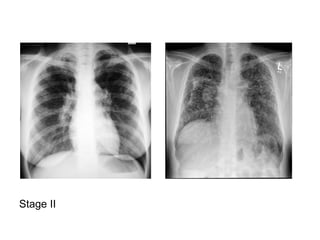

2-Classification :

-May be classified on a chest radiograph into 5

stages :

Stage 0 : normal chest radiograph

Stage I : hilar or mediastinal nodal enlargement

only

Stage II : nodal enlargement and parenchymal

disease

Stage III : parenchymal disease only

Stage IV : end-stage lung (pulmonary fibrosis)

Stage I

Stage II

Stage III

Stage IV